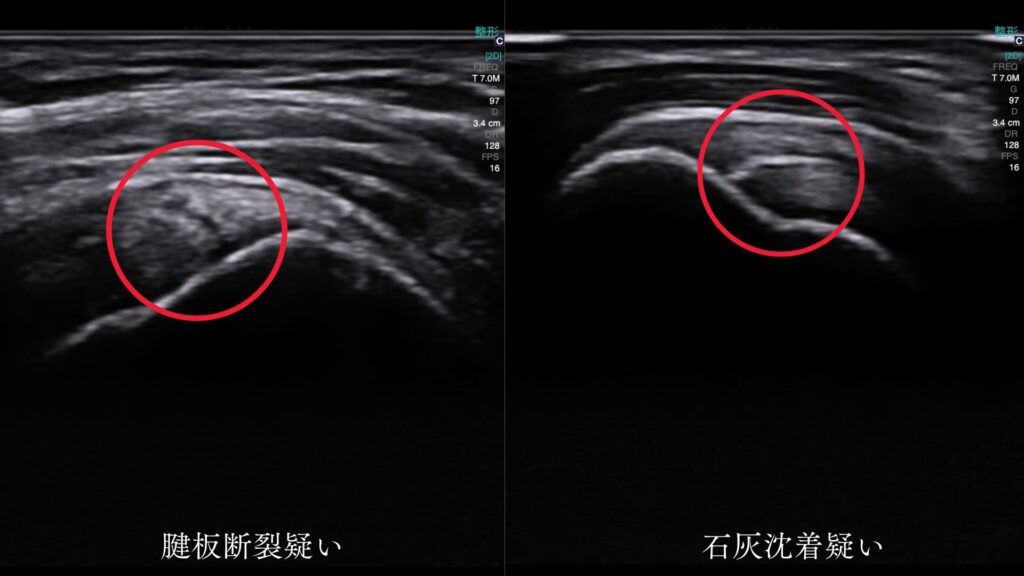

エコーによる腱板観察

当院では最新のエコー(超音波観察装置)を活用し、炎症や断裂の有無を確認します。レントゲンでは分かりにくい腱板の損傷も、リアルタイムで観察可能です。